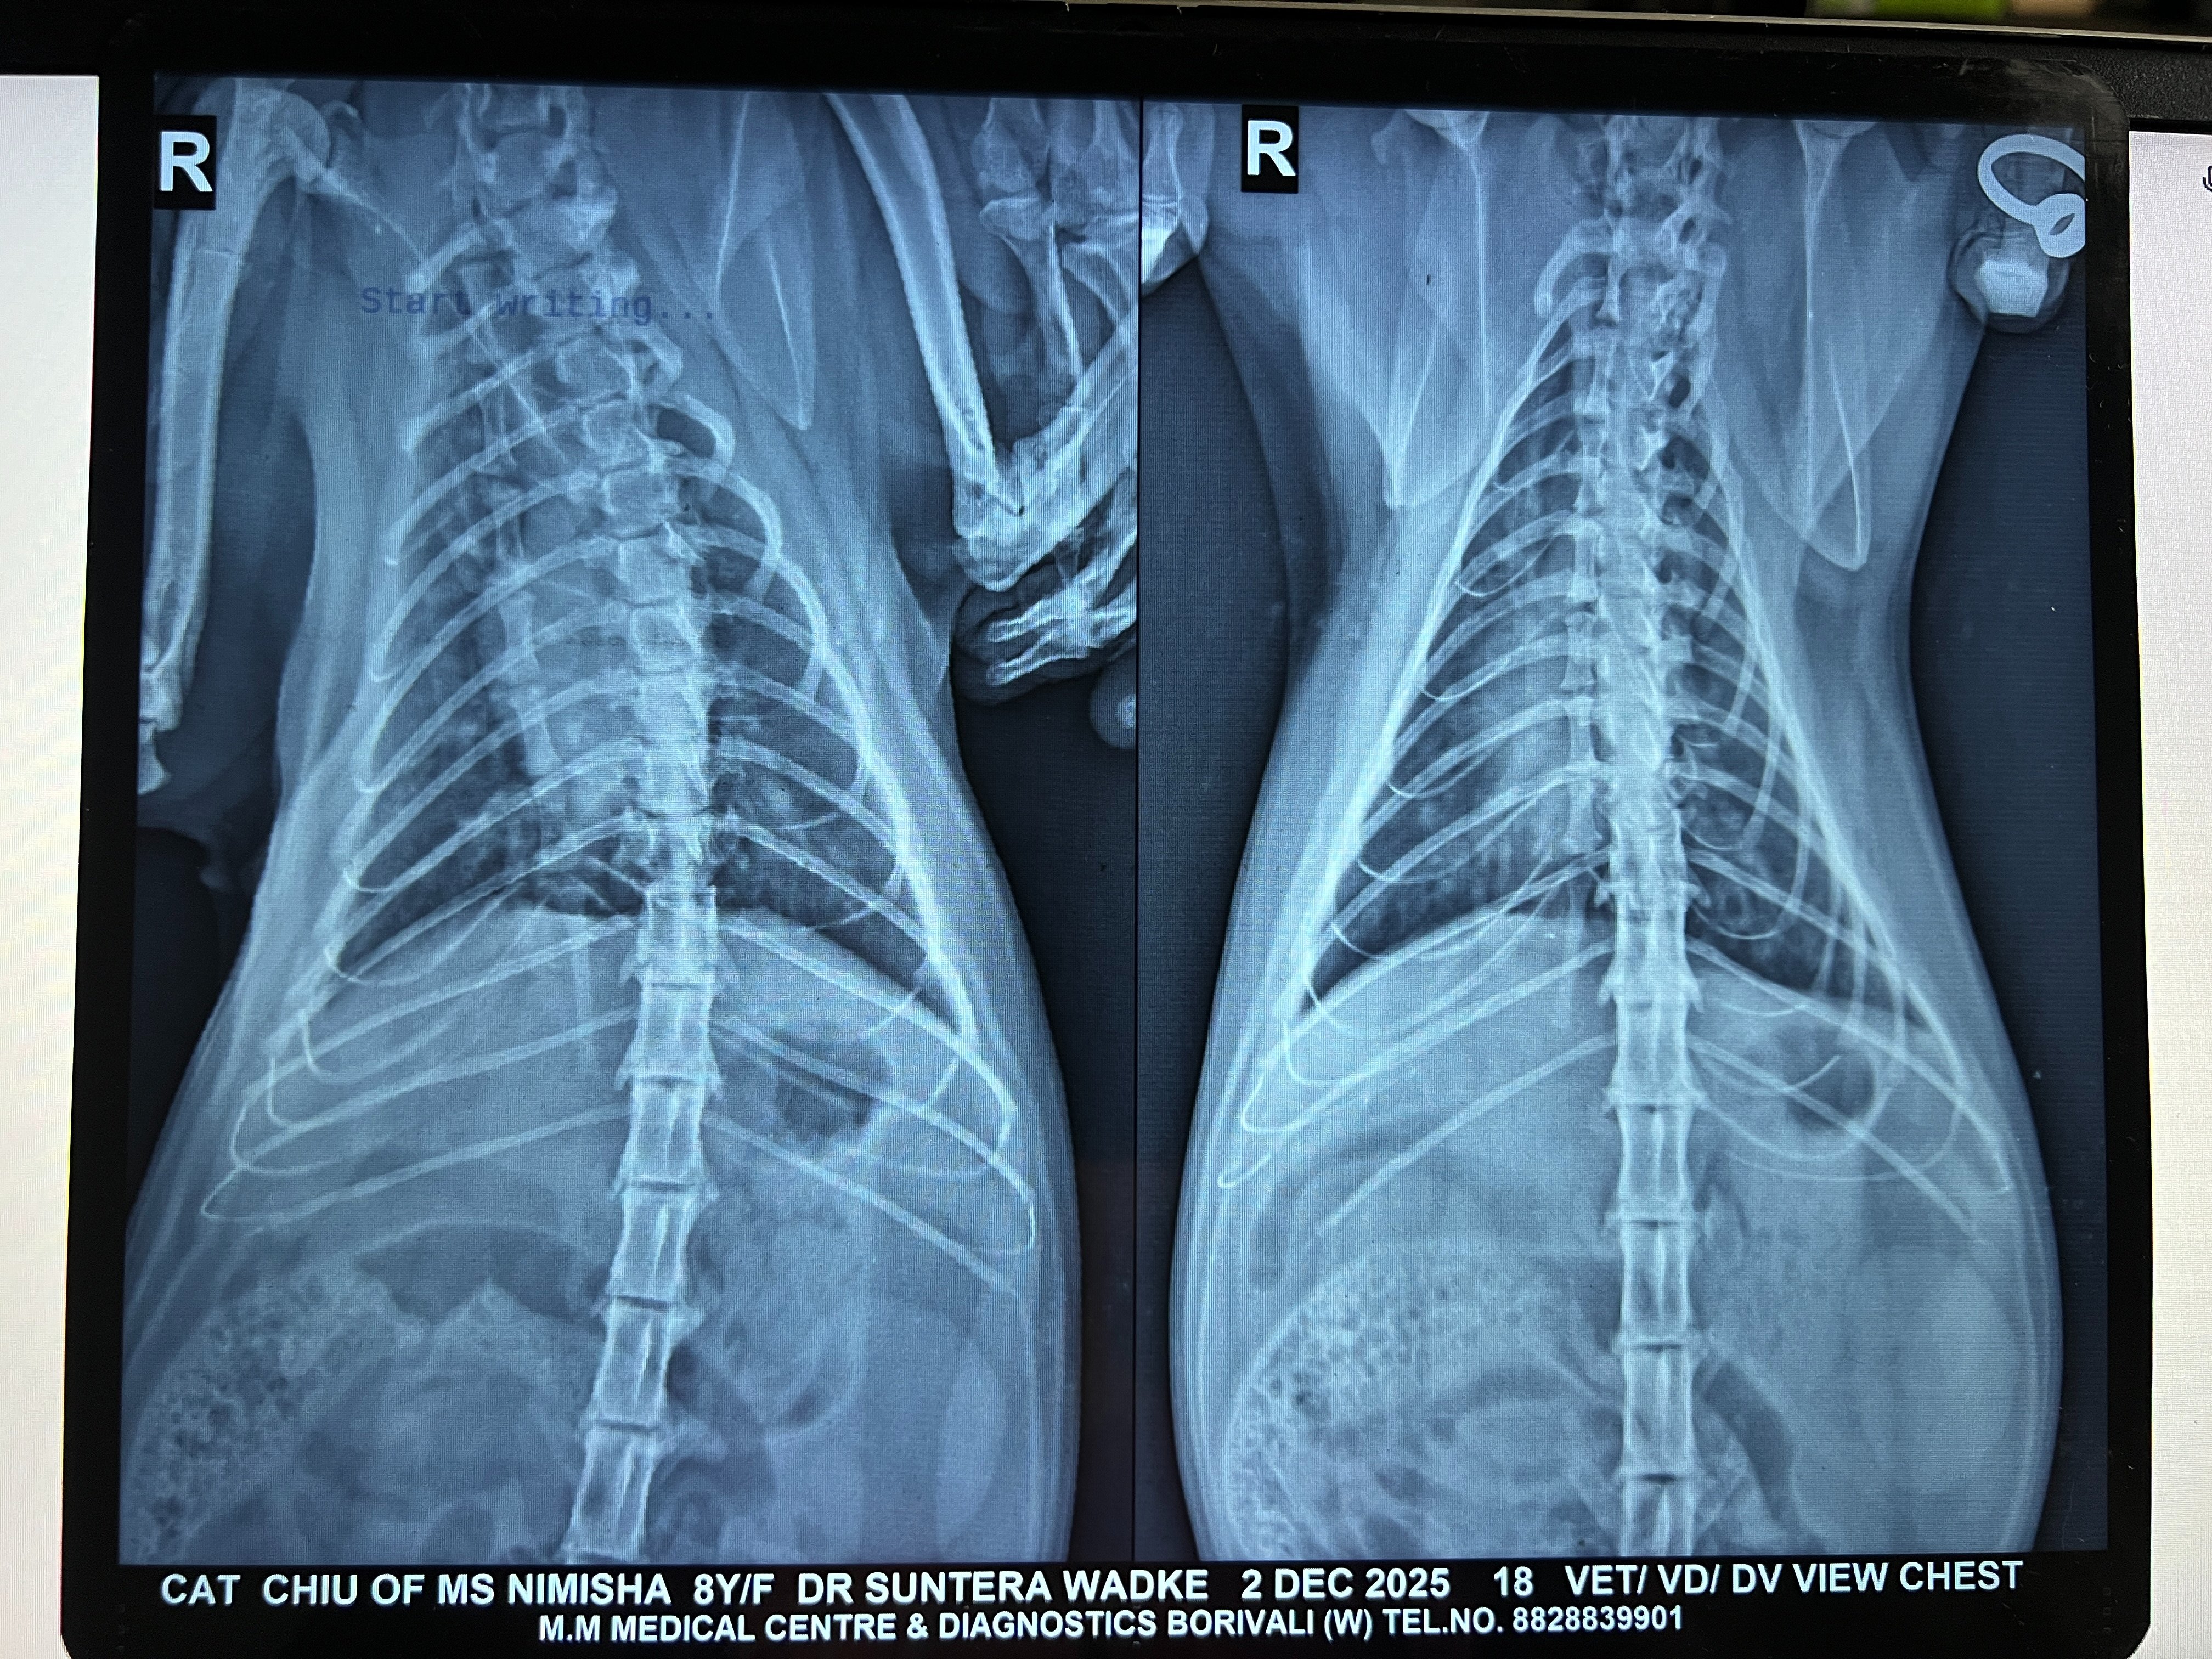

At this point, I decided to switch vets. The vet prescribed a combination of syrups (N-acetylcysteine and L-lysine)and nebulisation (Budesonide + Salbutamol 2.5 mg respules) for 15 days. There wasn't major improvement again and it felt like her wheezing had taken a new form, where I could hear some sort of phlegm but nothing would come out. We got an x-ray taken, vet felt the congestion had reduced and prescribed the same course along with Salbutamol/Asthalin syrup added and asked to repeat x-ray after 15 days.

I'm attaching her labs (Mar/Jul/Sep), x-rays (Aug/Sep/Nov/Dec) and 2d-echo (Dec).

3.2 Xray - DV VD - Chiu - 02Dec2025.jpeg2.6 MB · Views: 41 -

3.1 Xray - RT LAT - Chiu - 02Dec2025.jpeg2.4 MB · Views: 41 -